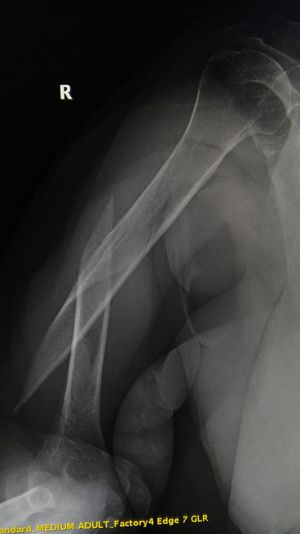

Xray

Fracture

Humerus